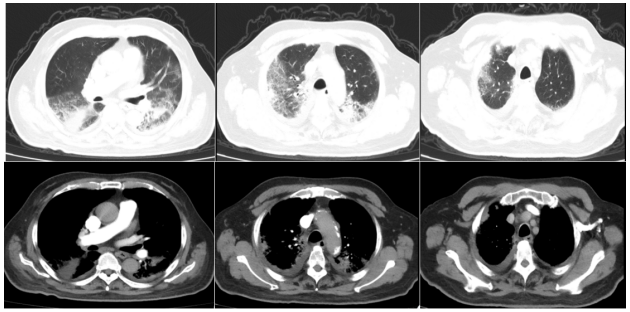

2025年2月7日胸部CT:双肺多发斑片状渗出及实变,双侧胸腔积液伴局部肺膨胀不全1

1  患者急诊胸部CT(2025-02-07)